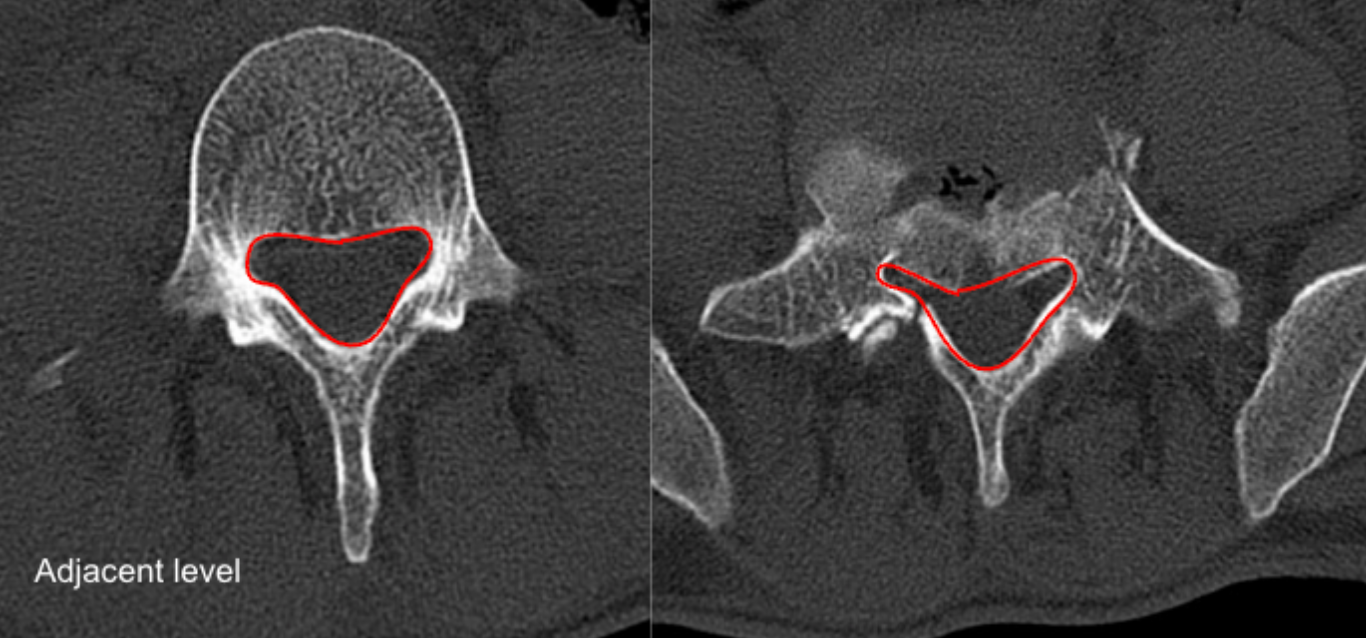

Canal Compromise Percentage estimates the proportion of the normal spinal canal that is occupied by retropulsed bony fragments following burst fracture. It is calculated by comparing the cross-sectional area (CSA) of the normal canal at an adjacent level with the residual canal area at the injured level.

Select Reference Level (Normal Canal)

• Choose the nearest intact level above or below the fracture.

• Use axial CT to outline the bony spinal canal.

• Measure cross-sectional area → A₀ (Normal Canal Area, mm²).

Select Injured Level

• Identify the level with maximal retropulsed fragments.

• Trace the remaining free canal lumen excluding bony fragments.

• Measure residual canal area → Aᵢ (Injured Canal Area, mm²).